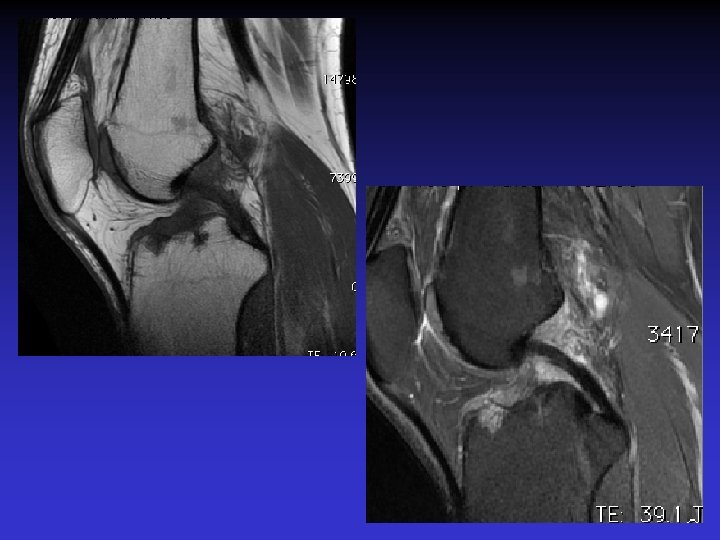

ASPECT IRM • • Hyposignal TI Hypersignal T 2 Pas de prise du contraste après Gado IV Continuité conservée du LCA+++ avec dilacération des fibres • Aspect en « tige de céleri »

GADO

GEODES SYNOVIALES • En regard des zones d’insertion fémorale et / ou tibiale • Hypo TI Hyper T 2 • Rehaussement possible après Gado IV